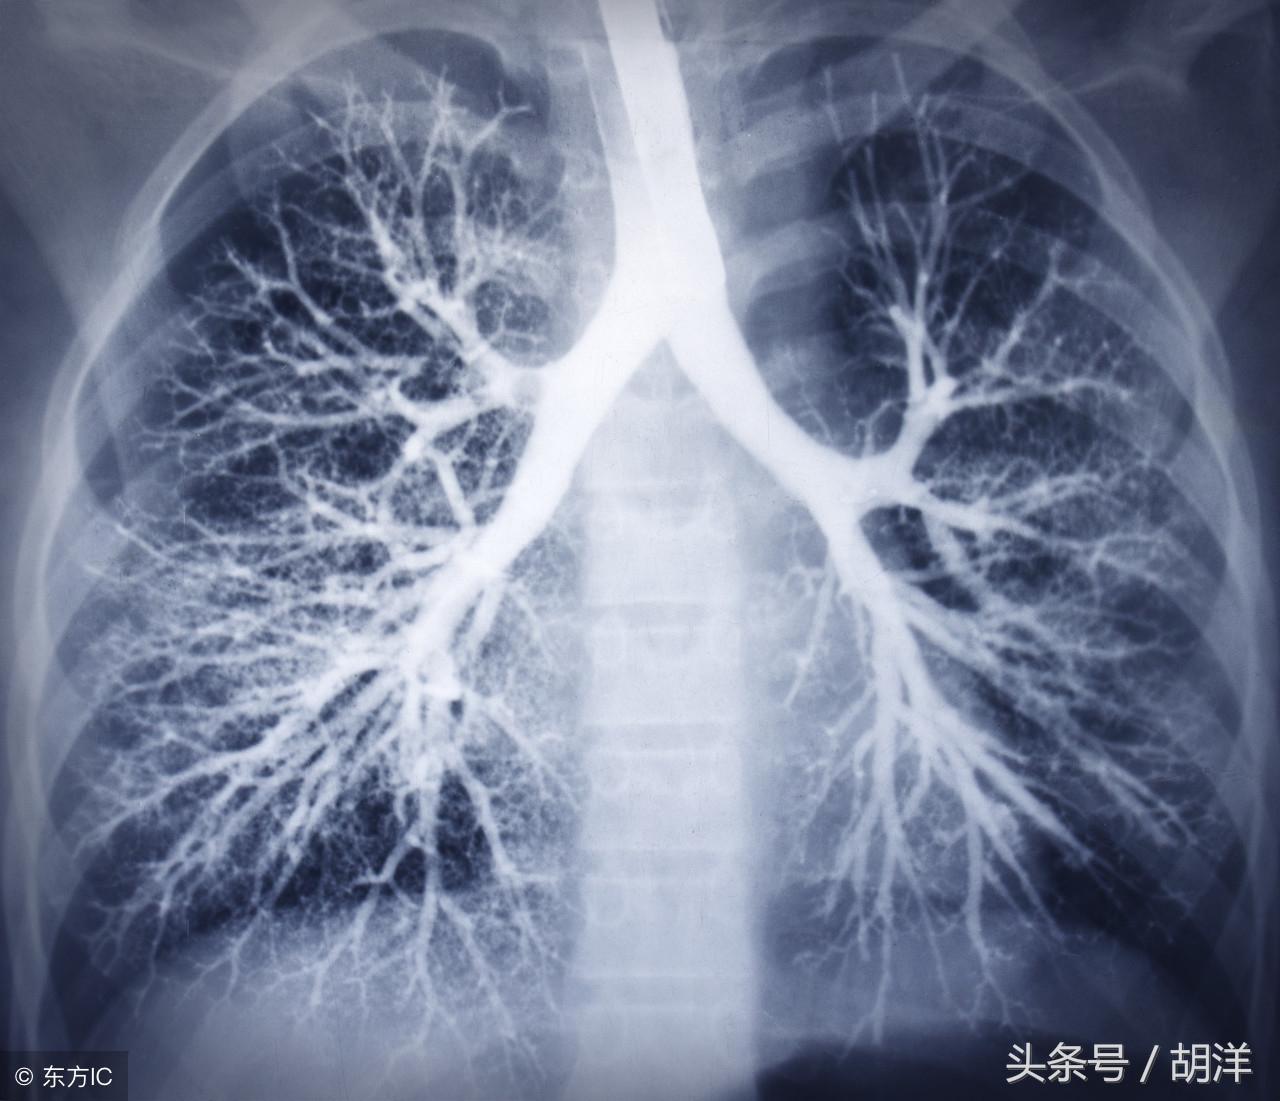

咳血又称咯血,是呼吸科一个比较严重的症状,由于其可能提示肺部肿瘤等严重疾病而受到重视,但事实上在引起咯血的病因中,肺部恶性肿瘤所占的比例并不是很大,但很多人因咯血而焦虑异常,特别是咯血久治不愈情况下,更加令人无法正常的生活和学习,那么哪些疾病可能导致反复发作痰中带血或者咳出满口鲜血呢?

支气管扩张是一种支气管管壁结构破坏性疾病,正常情况下,支气管是一个带有弹性,拥有一定管径的能够维持正常呼吸通气的结构,当管壁结构受到破坏时,气管会受到被动的牵拉而扩张,管壁的血管由于弹性较小,容易被撕扯呈血管瘤改变,一旦胸腔内血流压力增大可能冲破血管瘤变薄的管壁而导致大咯血,少量渗血时则呈现为痰中带血。

肺结核是一种肺部传染性疾病,是由于结核菌在肺部生长并破坏肺部结构导致的,对于肺部的损害很大,寄生的肺组织局部甚至会完全毁损形成干酪样坏死物排出体外,这样的破坏难免侵蚀血管导致出血,也是大咯血的原因之一。

肺癌也是较为常见的导致咯血的原因,恶性肿瘤细胞对于肺组织的侵蚀是其他疾病无法比拟的,几乎可以侵犯肺部正常组织中的所有结构,包括血管,另外,肺癌癌肿由于生长过快,其表面的细胞可能会因为得不到充足的血液供应而坏死,这样的坏死很容易产生渗血,是引起痰中带血的常见原因。

肺炎引起咯血的原因和肺结核类似,都是由于肺部细菌感染后破坏正常肺结构引起渗血以及血管破裂所致。